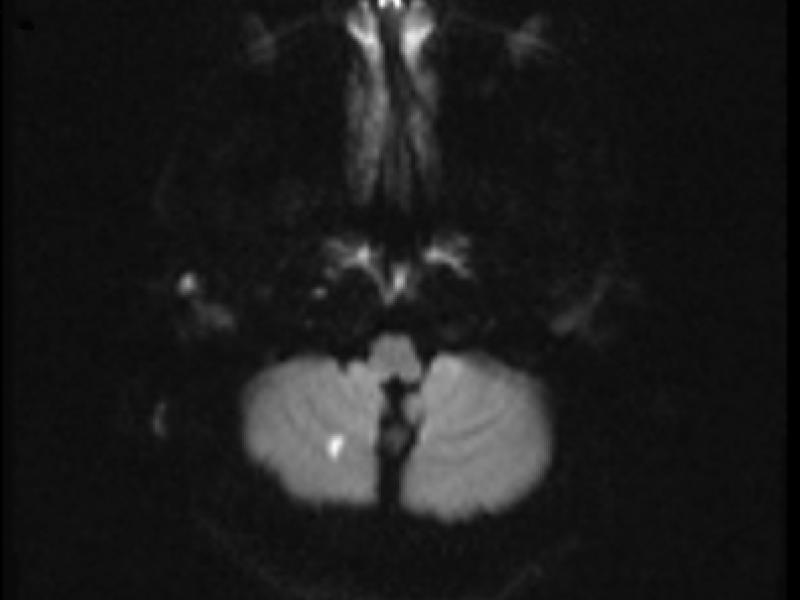

What's the diagnosis? By Dr. Eric Chavis

A 24 yo male presents with headahce and feeling unsteady